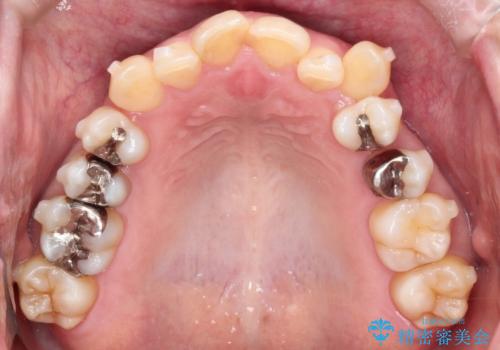

【インビザライン】重度叢生をなおしたい

- 全体的に歯並びをなおしたいことを主訴に来院されました。

上顎前歯が舌側傾斜していたため少し拡大を行いながら非抜歯で治療を行っています。

マウスピースをしっかり使用していただいたので、きれいな歯並びになりました。